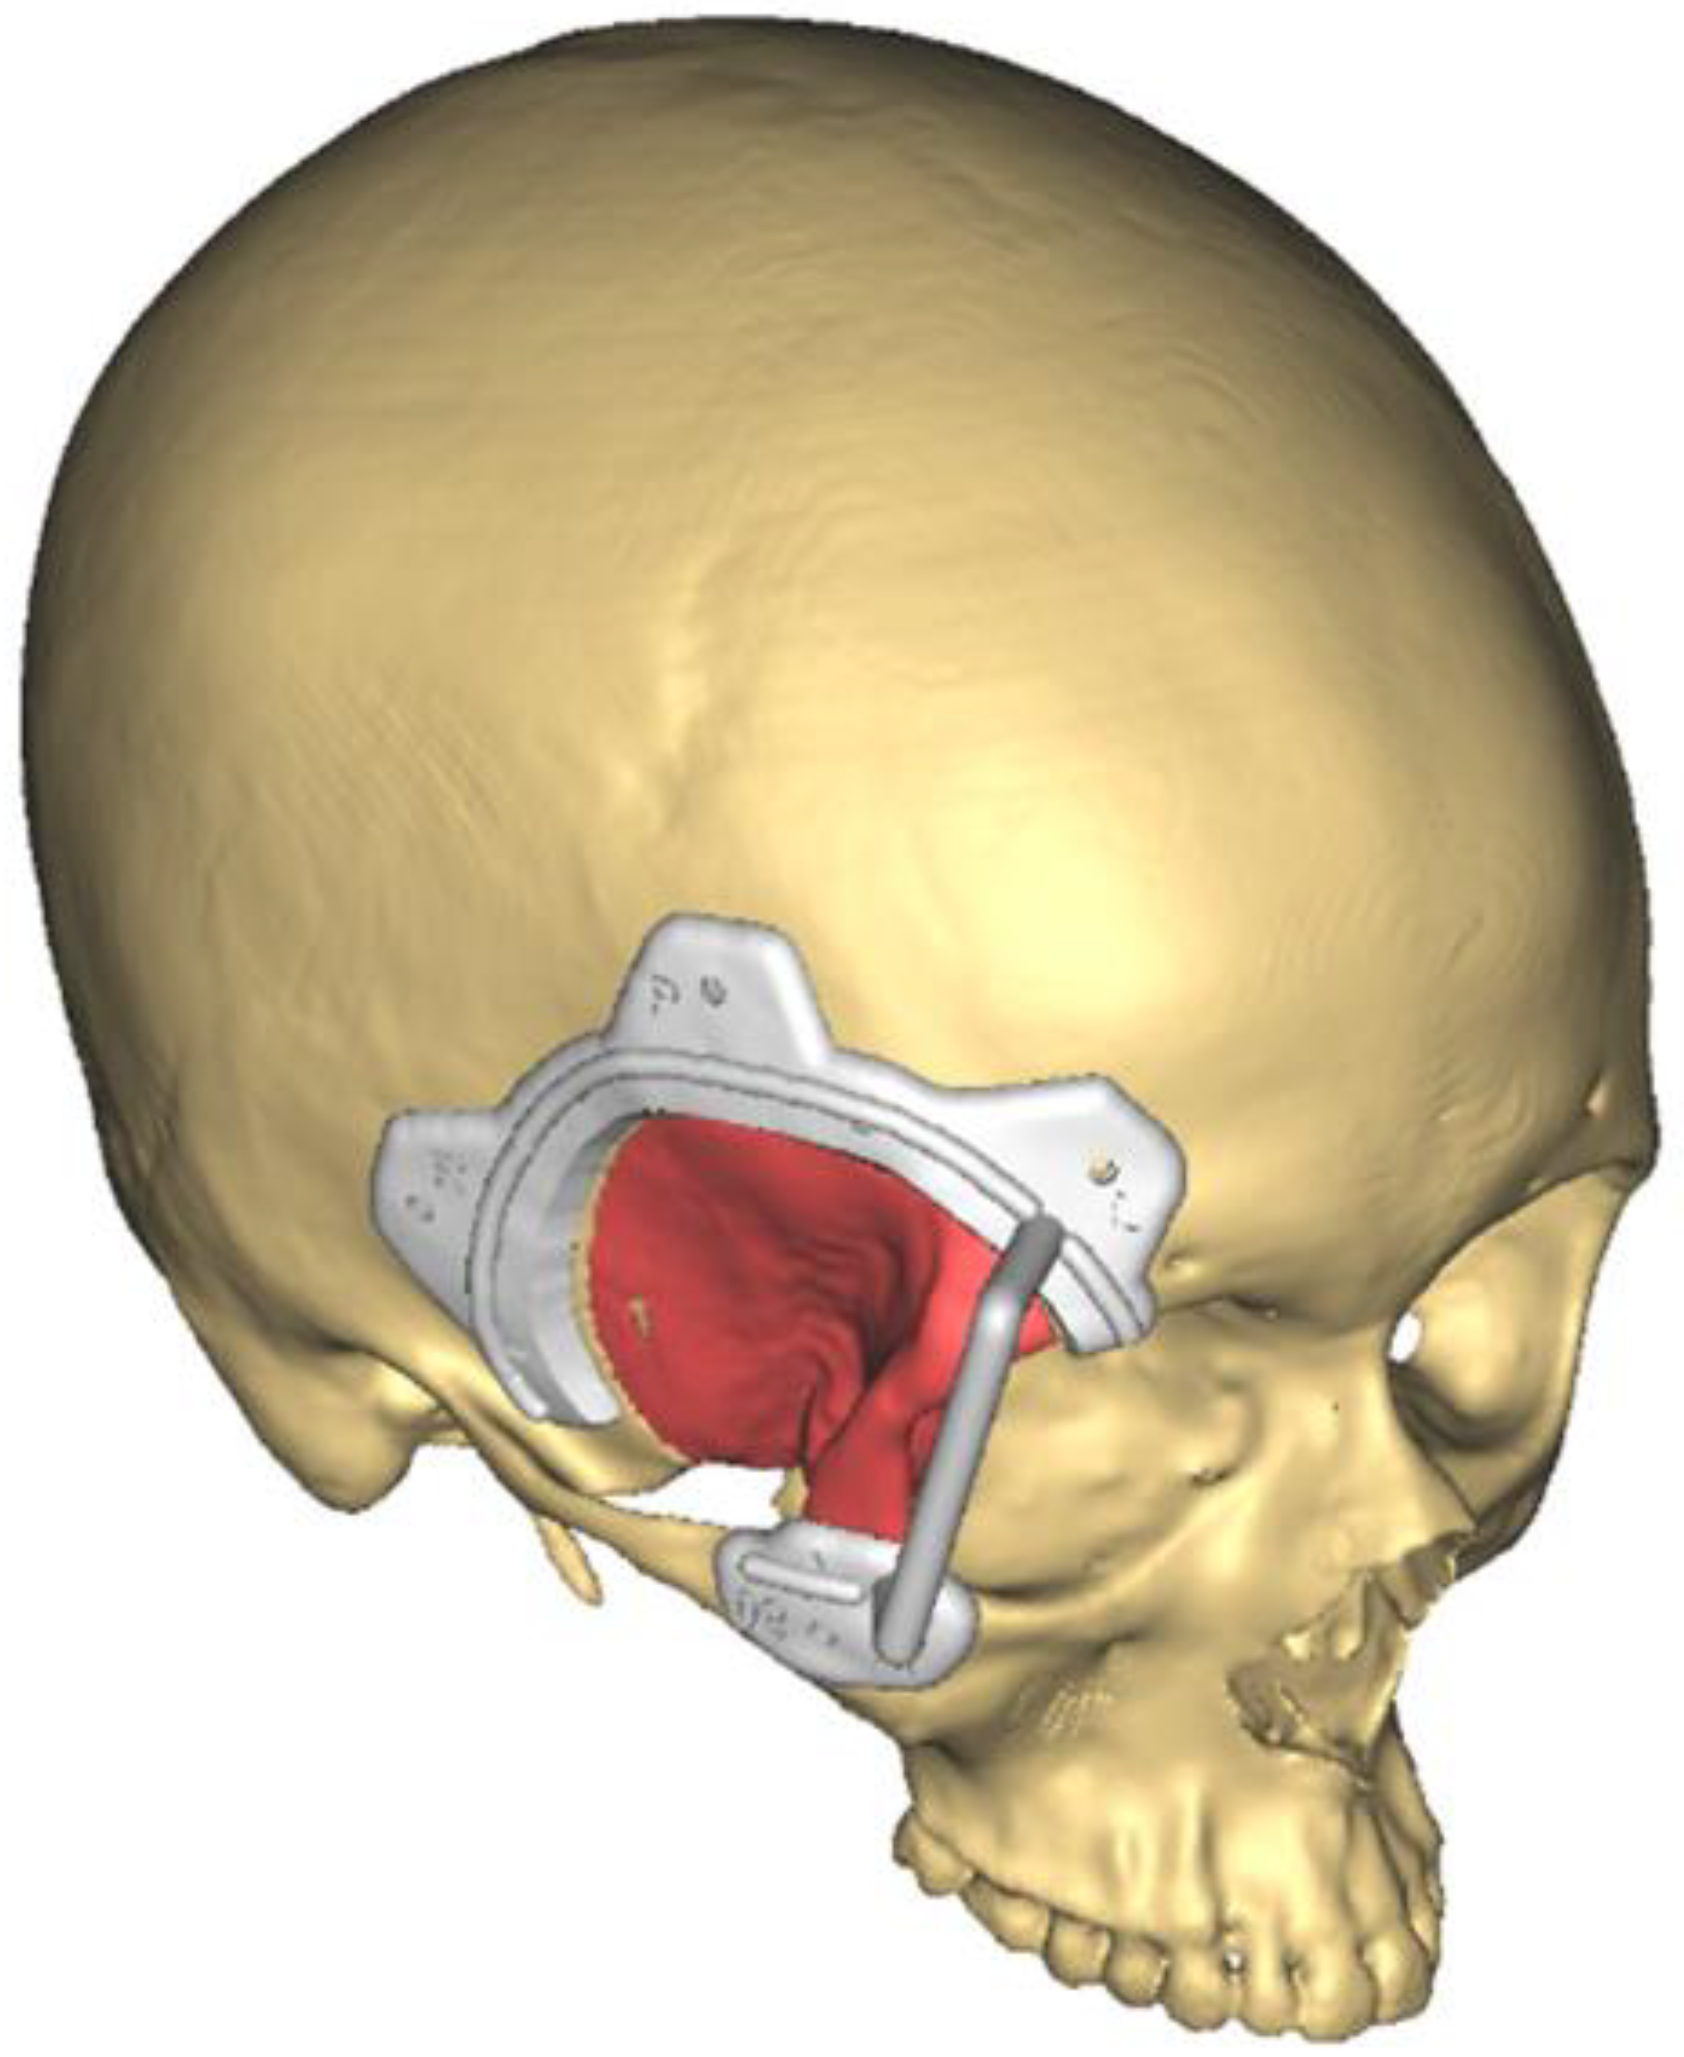

2.2. Preoperative Study and Virtual Surgical Planning

4.2. Surgery Virtual Planning: CAD CAM Technology

4.3. Reconstruction with Patient-Customized Implants (PSIs)